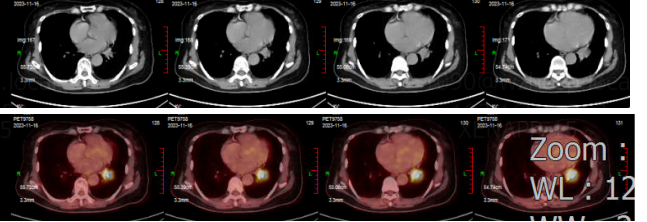

• 2025年4月1日:PET-CT提示肿瘤复发、转移,无进展生存期(PFS)为15个月。对比2023年11月PET-CT显像,①左肺下叶前内基底段软组织结节,糖代谢增高,对比前片病灶缩小、代谢减低,提示肺癌治疗后,肿瘤活性存留;②右侧颈部IV区、纵隔1R/2R/4R组多发淋巴结肿,糖代谢增高,提示转移性淋巴结,前片所示纵隔7组淋巴结消退;③颅脑未见异常放射性浓聚灶。

图片6.png

PET/CT(上:2025年4月1日;下:2023年11月16日)